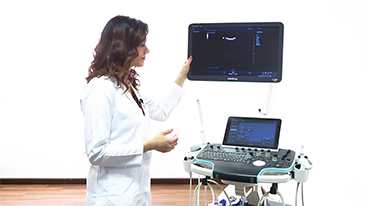

???19 - ??? ????? ?? ??

??? ????? ?? ??? ???? ??? ???? ??? ????, ?? ?? ??(PPE)? ??? ??, ? ??, ??? ?? ??? ???? ??? ?? ??? ??????. ???? ???? ??? ??? ??? ?? ??? ???? ?? ?? ?? ???? ?? ?? ??? ?? ???? ???? ?? ?? ?? ??(POC) ? ??? ??? ? ? ?????.